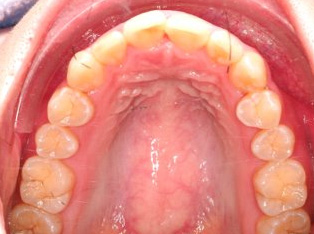

治療前

治療終了前